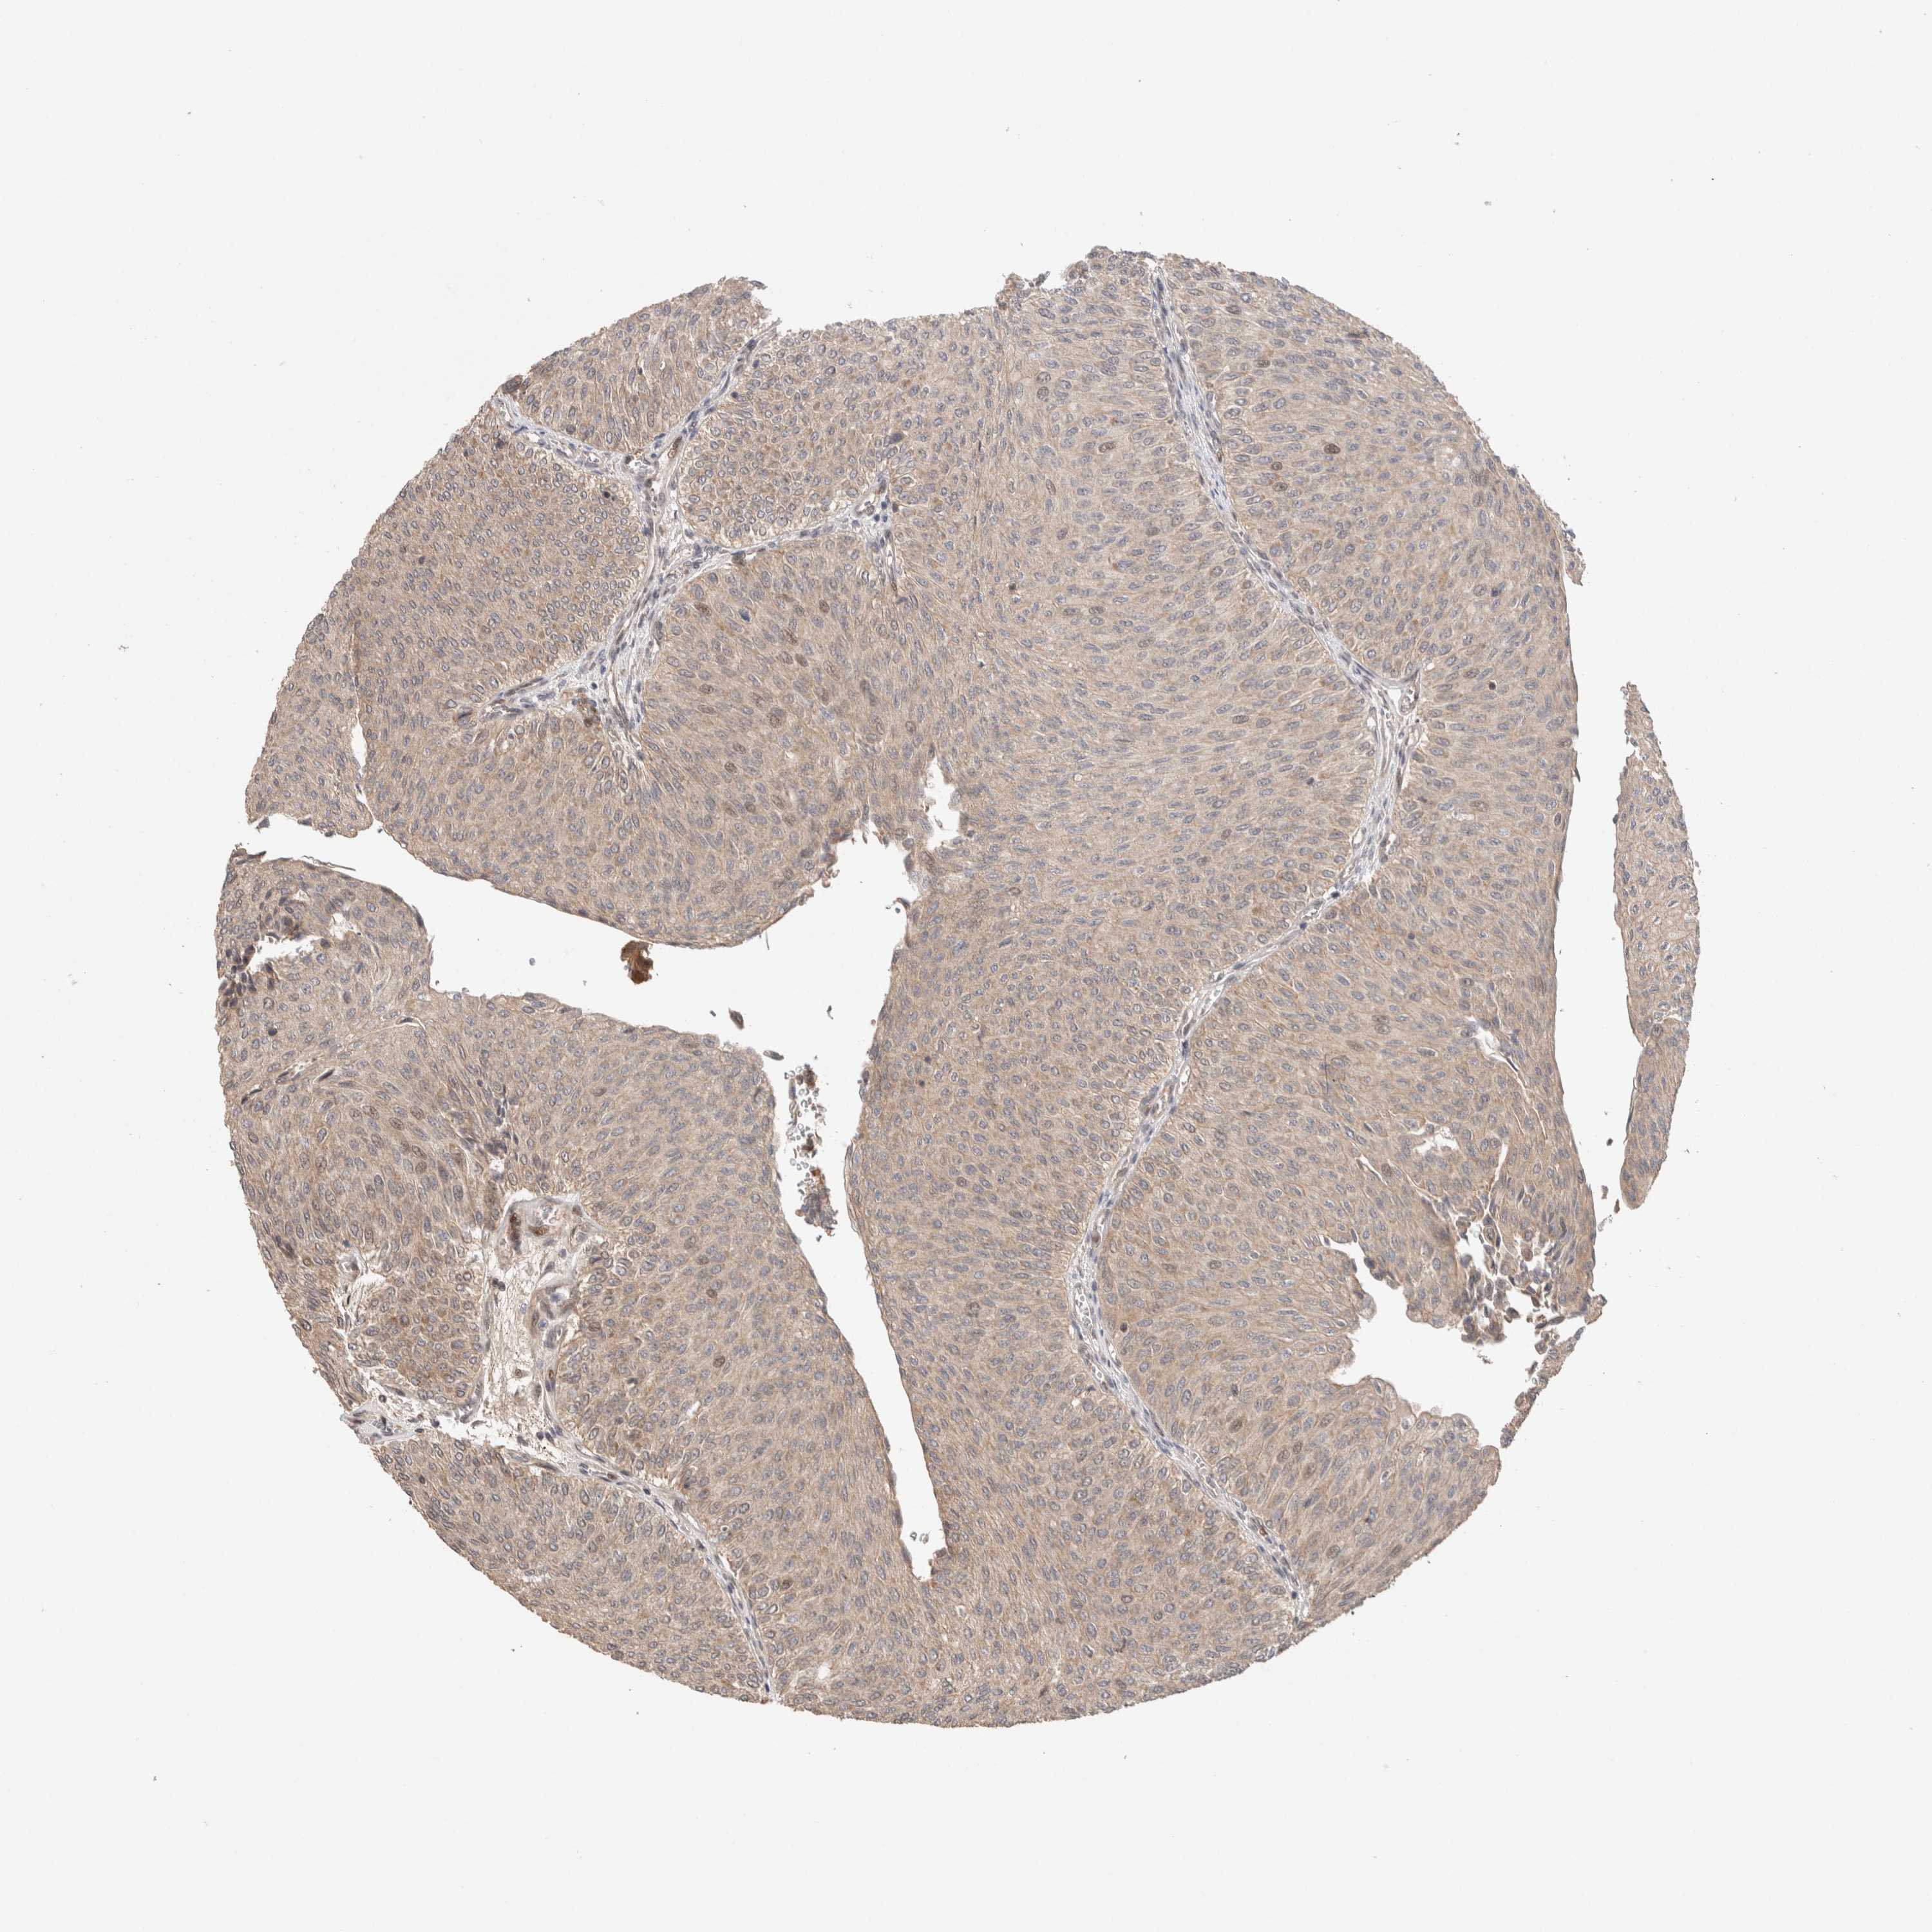

UROTHELIAL CANCER - Protein expressioni

A mouse-over function shows sample information and annotation data. Click on an image to view it in a full screen mode. Samples can be filtered based on level of antibody staining by selecting one or several of the following categories: high, medium, low and not detected. The assay and annotation is described here.

Note that samples used for immunohistochemistry by the Human Protein Atlas do not correspond to samples in the TCGA dataset.

Antibody stainingi

Antibody staining in the annotated cell types in the current human tissue is reported as not detected, low, medium, or high, based on conventional immunohistochemistry profiling in selected tissues. This score is based on the combination of the staining intensity and fraction of stained cells.

Each image is clickable and will lead to virtual microscopy that enables deeper exploration of all samples and also displays staining intensity scores, fraction scores and subcellular localization as well as patient and tissue information for each sample.

Antibody HPA024268

Staining

High

Medium

Low

Not detected

Intensity

Strong

Moderate

Weak

Negative

Quantity

>75%

75%-25%

<25%

None

Location

Urothelial carcinoma, Low grade

Urothelial carcinoma, High grade